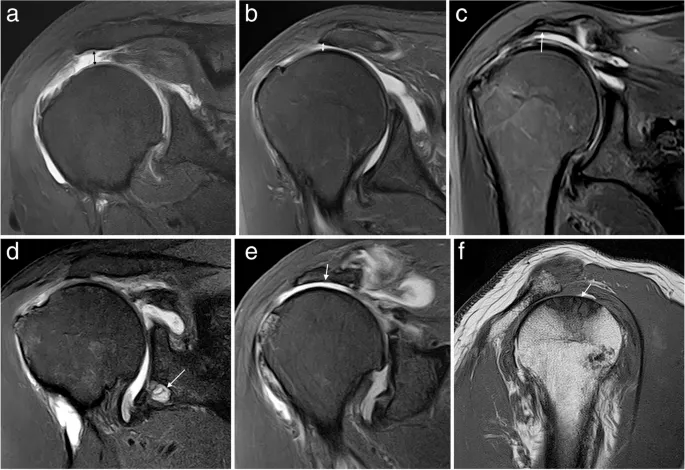

- MSK - Shoulder:

- Rotator Cuff: Supraspinatus, infraspinatus, teres minor, subscapularis. Tears, tendinopathy (↑ signal, thickening).

- Labrum: Glenoid labrum tears.

- Biceps tendon: Tenosynovitis, tears.

⭐ Fluid-sensitive sequences like T2-weighted with fat suppression (T2 FS) or STIR are crucial in MSK MRI for detecting edema, inflammation, and fluid in ligamentous/meniscal tears.